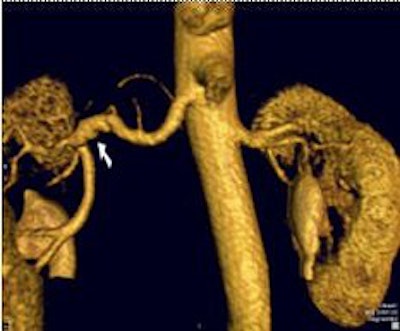

| Targeted MIP (20 mm) from same patient as above. By applying parallel acquisition with an acceleration factor of 3, the 3D dataset was acquired with 0.8 x 0.7 x 0.9 mm³ voxels over a 420-mm field-of-view, during a 19-second breath-hold. Note the branch stenosis at the origin of the left inferior pole renal artery. |